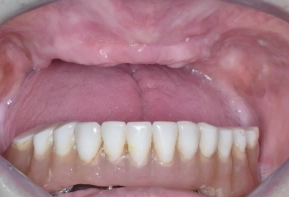

In this case presentation, the patient

suffered from a failed dentition in the maxilla and is planned to be restored with an

implant retained fixed hybrid denture. This video demonstrates the step-by-step

approach of the implant placement in the maxilla, including a titled implant

to avoid the sinus. Plaster impression was taken immediately after surgery and

an immediate temporary metal-acrylic denture was fixed to the implants.